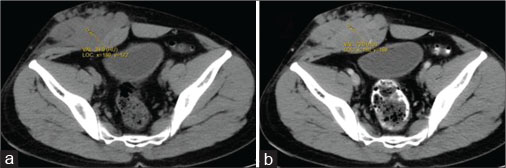

A 40-year old male patient presented with swelling over the anterior abdominal wall on the right side in lower abdomen for 1 month which was rapidly increasing in size. There was a history of weight loss. The mass was painless. The ultrasonography showed a large, well-defined solid mass with lobulated outlines in anterior abdominal wall in the right paraumbilical and hypogastric region [Figure 1]. The mass was seen in the subcutaneous plane, causing extrinsic compression on adjoining right rectus abdominis and external oblique muscle. It was predominantly hypoechoic with small areas of the necrosis in its center and showed mild vascularity on color Doppler. No calcification was seen. Plain and contrast enhanced computed tomography (CT)-scan of the abdomen and pelvis was performed. A large, well defined solid mass with lobulated outline measuring approximately 96 mm × 38 mm × 98 mm in transverse, anteroposterior and craniocaudal dimension was noted in the anterior abdominal wall on the right side in right iliac region extending to hypogastric region. It was slightly hypodense with respect to muscle on the plain study with a CT value of 35–45 HU and showed a mild heterogeneous enhancement in contrast study (CT value 55–65 HU). No calcification was noted. The mass was in subcutaneous plane and was extending anteriorly up the skin. Posteriorly, it was causing mass effect on the right rectus abdominus and adjoining external oblique and internal oblique muscles which were compressed and displaced posteriorly with obliteration of intervening fat planes [Figure 2]. An enhancing vessel was noted in the right rectus abdominus extending into the mass suggestive of neovascularity. No intra-abdominal extension was noted. Rest of the abdominal wall appeared normal. No hepatic or adrenal metastases, intra-abdominal lymphadenopathy noted. On magnetic resonance imaging (MRI), the mass appeared slightly hyperintense with respect to muscle on T1-weighted image, heterogeneously hyperintense on T2-weighted image (T2WI), and hyperintense on short tau inversion recovery and showed restricted diffusion on diffusion-weighted imaging with low apparent diffusion coefficient (ADC) values (ADC = 800). It was causing mass effect on the right rectus abdominus and adjoining external oblique and internal oblique muscles [Figure 3] [4] [5] [6].

| Figure 2: Computed axial tomography of abdomen - plain (a) and contrast (b) showing well-definedsolid mass with lobulated outlines in the right iliac fossa and hypogastric region in subcutaneous plane causing extrinsic compression and posterior displacement of abdominal wall muscles appearing slightly hypodense on plain study (a) showing heterogeneous enhancement in contrast (b)